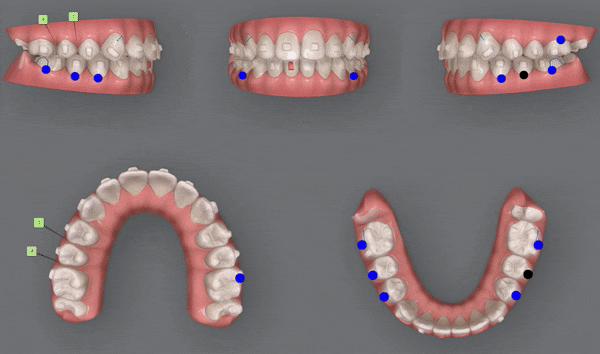

인비절라인은 '클린체크' 프로그램을 통해

초기 상태부터 치료를 마친 최종 상태까지

모든치료 단계를 시뮬레이션하고

치아의 미세한 움직임까지 3D컨트롤 할수 있으며

원장님의 진단 내용을 치아 이동에 바로 반영할 수 있도록 하며

교정 순서, 방향, 속도, 장치 갯수 등 원장님의 치료과정을 컨트롤할 수 있습니다.

1st (40개)

첫번째 클린체크의 영상입니다.

인비절라인의 장점 중의 하나는

교정 후의 모습을 예측할 수 있는것 입니다.

원장님께서 클린체크 디자인을 마치게 되면

인비절라인 교정치료 후에

치아이동이 어떻게 변화하는지 클린체크를 통해 확인 해 볼 수 있는것인데요.

클린체크대로

치아들이 움직이면서 점점 가지런해 지는게 보이시나요?

첫번째 클린체크에서는 총 40개의 장치로

진행 해드렸습니다.